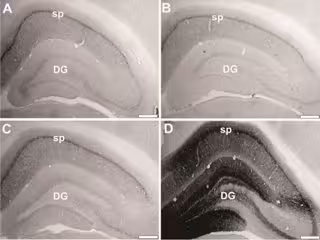

GANT Y OTROS, JNEUROSCI (2017)

Philip Landfield, John Gant, Eric Blalock y sus colegas de la Universidad de Kentucky, en Lexington, Estados Unidos, encontraron que el tratamiento a corto y largo plazo de ratas envejecidas que induce la sobreexpresión de la proteína FK506 Binding 12.6/1b (FKBP1b) restableció la expresión de más de 800 genes afectados por el envejecimiento comparable a la de las ratas jóvenes sin tratamiento, además de mejorar el rendimiento en una tarea de laberinto de agua.

Los genes restaurados representan una nueva red genómica que regula la integridad de la estructura neuronal en el hipocampo y que es el objetivo del envejecimiento. Estos resultados sugieren que abordar la deficiencia de FKBP1b puede representar una nueva vía para contrarrestar la pérdida de memoria relacionada con la edad.